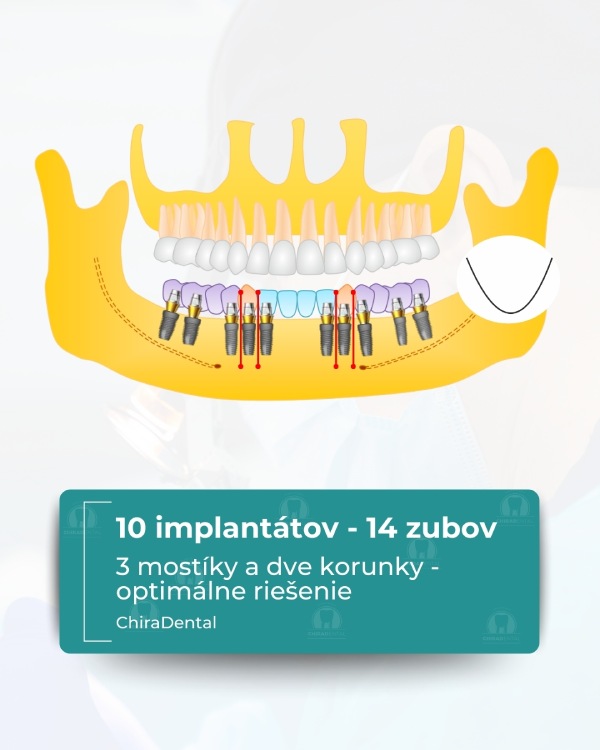

⭐ Možnosť 3 — Prémiové (10 implantátov)

Najspoľahlivejšia a najkomplexnejšia rehabilitácia, ktorá zabezpečuje vynikajúcu pevnosť a trvanlivosť.

V cene:

Inštalácia 10 implantátov so súčasnou augmentáciou kosti a korekciou mäkkých tkanív;

Odtlačky pre dočasnú rekonštrukciu sa robia nasledujúci deň;

Dočasné zuby sa fixujú za 3-5 dní.

Výsledok: 14 dokonale rozmiestnených zubov. Konečná rekonštrukcia po 3-6 mesiacoch: — kovovo-keramická alebo zirkónová, — konštrukcia je rozdelená na 3 mostíkové segmenty (centrálny + dva bočné), čo zaisťuje dokonalú stabilitu a jednoduchú údržbu.